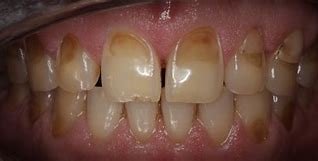

3. Erosion

Dental erosion involves the chemical dissolution of tooth structure through acid exposure, absent of bacterial involvement. Sources of acids include:

Erosion characteristically presents as smooth, shiny surfaces with cupped-out lesions on occlusal surfaces and thinning of enamel on facial and lingual surfaces.

Case Study 1: Combined Erosion and Attrition

Patient Profile: 45-year-old male with complaints of increasing sensitivity and esthetic concerns related to shortened anterior teeth.

Clinical Findings:

- Generalized thinning of enamel on palatal surfaces of maxillary anterior teeth

- Cupped-out lesions on first molars

- Flattened incisal edges with matching wear facets

- History of GERD and occasional clenching reported during stress periods

Diagnostic Assessment: Combined erosion from GERD and attrition from stress-related clenching.